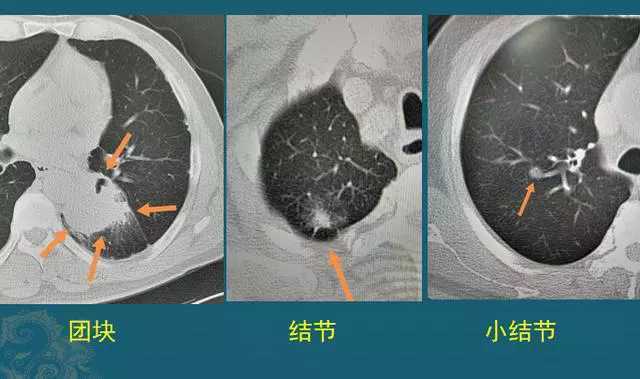

这个简单提一下,肺部孤立性病灶,直径>3cm的叫肿块(团块),直径介于1-3cm的叫结节,而直径<1cm的叫小结节。如下图:

以后大家看医生的报告单,对团块和结节的大小就心中有数了。我们今天只聊肺结节,因为肿块的良恶性比较容易诊断。